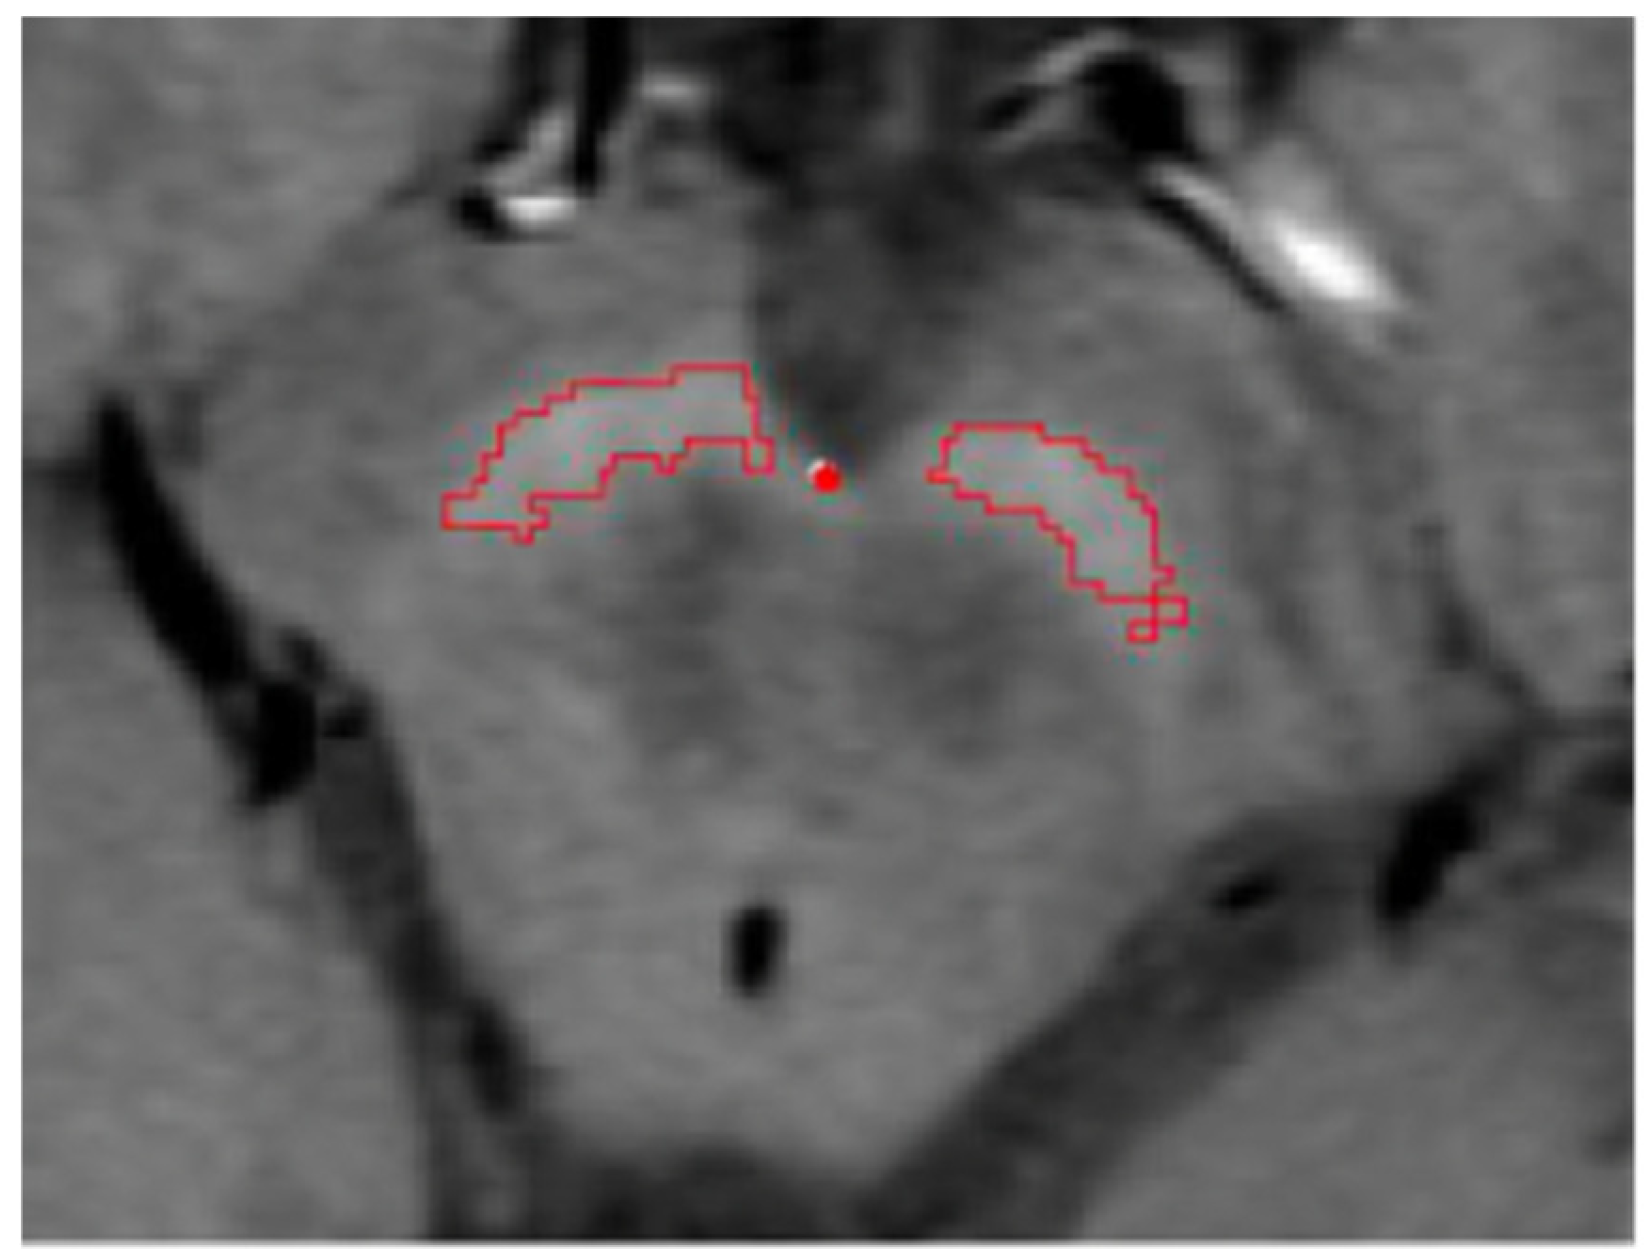

2.4.1. Semi-Automated Segmentation

2.4.3. Volume Measurement

2.4.4. Volume Correction